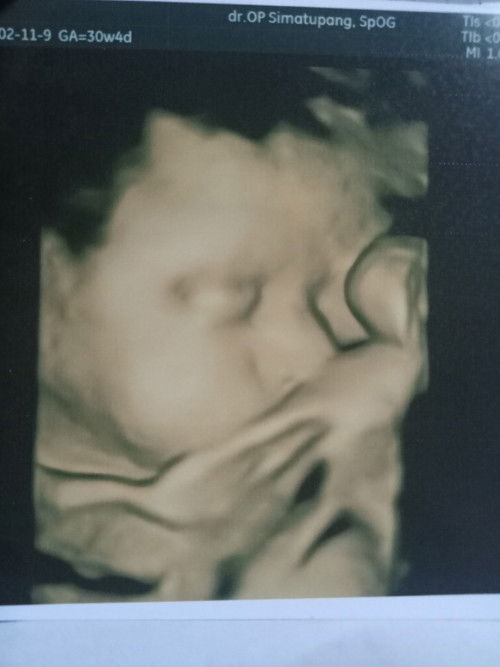

Bbj kurang

Kmrin hbis usg usia 30w4d tp bbj cuma 1.1 tips dong bun supya bbj cpet naiknya